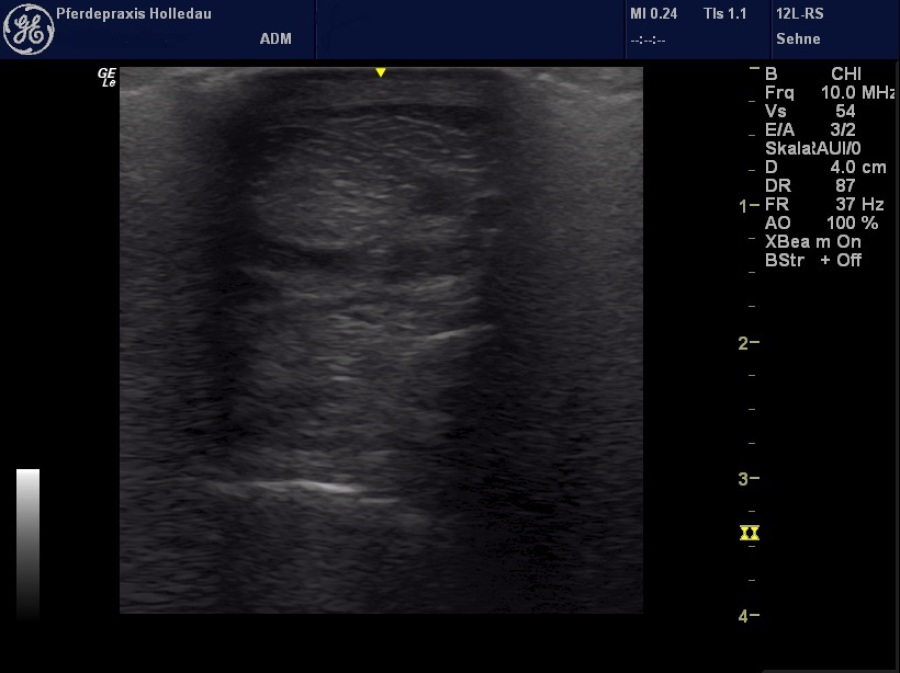

Um eine genaue Diagnose zu stellen, ist meistens der Einsatz von bildgebenden Verfahren nötig. Da aufgrund der sorgfältigen klinischen Untersuchung meist bereits ein Verdacht geäußert werden kann, schließt sich je nach dem eine Röntgen- oder Ultraschalluntersuchung an. Beim Röntgen werden in erster Linie knöcherne Strukturen beurteilt, die wichtig sind für eine Diagnosestellung bei Erkrankungen wie Gelenk-Chips, Arthrosen, kissing spines, Hufrehe, Hufrollen-Syndrom, Spat etc. Bei einer Ultraschalluntersuchung werden die Weichteilstrukturen beurteilt, unter anderem Sehnen, Sehnenscheiden, Bänder, Muskeln, Gelenksfüllung und falls zugänglich auch Blutgefäße, Nerven, Gelenkkapseln, Knorpelstrukturen und Knochenoberflächen.